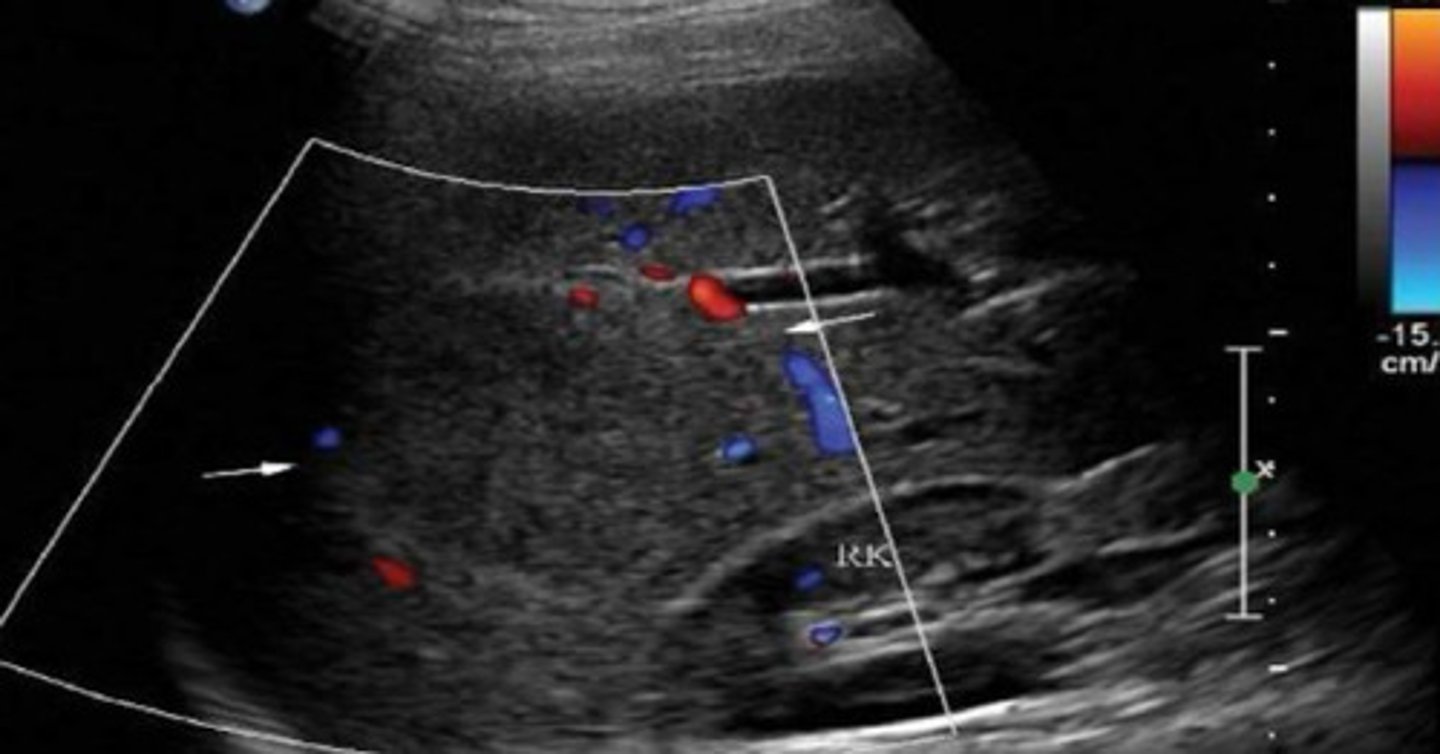

Normal sonographic appearance of liver and kidney

What does this image represent